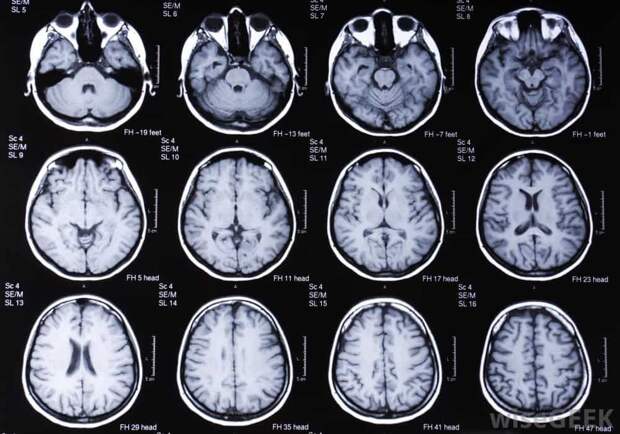

Процедура абсолютно безболезненна и не требует специальной подготовки со стороны пациента. Во время проведения МРТ пациент располагается внутри специального аппарата, где происходит сканирование исследуемой области под воздействием сильного магнитного поля.

Полученные изображения позволяют врачу выявить патологические изменения тканей головного мозга, что способствует постановке точного диагноза и назначению адекватной терапии.